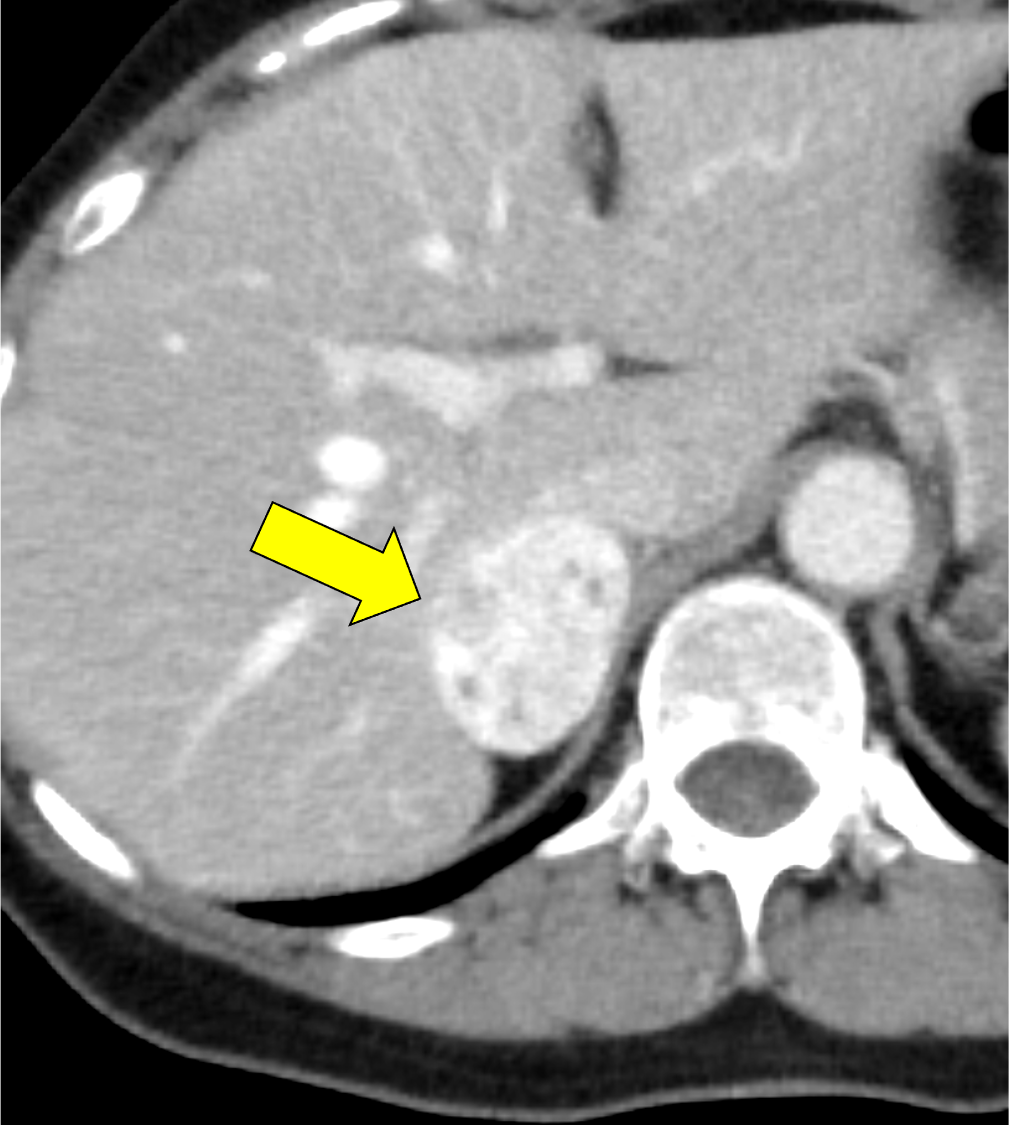

褐色細胞腫は副腎髄質に存在するクロム親和性細胞に由来する腫瘍で、カテコールアミンなど種々の生理活性物質を産生する。ダイナミック造影で動脈相での強い濃染と持続する造影効果が特徴とされ、サイズが大きい病変は嚢胞変性や出血、壊死を伴うことが多い。かつては、臨床的に褐色細胞腫が疑われる場合、ヨード造影剤の投与はカテコールアミンの過剰放出を誘発し、高血圧クリーゼを引き起こす可能性があるため原則禁忌とされていた。しかし、現在汎用されている非イオン性・低浸透圧性造影剤であればこの現象は起こらないとの報告もあり、European Society of Urogenital Radiology Guidelines on Contrast Media, ver 10.0では、「経静脈的ヨード造影剤の投与をする場合でも特別な準備の必要はない」と記載されている。イオプロミドの電子添文上は、禁忌にはなっていないものの、「慎重に投与すること」との記載になっている。本例では、血管腫疑いとして合計5回の造影CTが行われているが、血圧変動や頭痛、動悸などの症状は一度も認められなかった。

本例の画像所見として、褐色細胞腫としてダイナミック造影の濃染パターンは典型的ともいえたが、大きさの割に変性が乏しい点、MIBGシンチでの核種集積に乏しい点、ホルモン産生に乏しい点など非典型的な要素が複数存在し、海綿状血管腫を除外しきれなかった。なお、褐色細胞腫はRET遺伝子変異による多発性内分泌腺腫症(multiple endocrine neoplasia;MEN)type 2A・2B、VHL遺伝子によるvon Hippel-Lindau病、NF1遺伝子による神経線維腫症1型に生じることが知られているが、これらの疾患を想起させるような他病変は本例には見つかっていない。

腺腫や骨髄脂肪腫など良性と断定できない副腎腫瘍の鑑別をする際、大きい病変であれば褐色細胞腫や副腎癌、悪性リンパ腫などが考慮される。核医学検査も有用ではあるが、本例のように偽陰性となることも稀にあり、その際はダイナミック造影パターン、血管への浸潤、転移の有無などから判断しなければならない。適切なタイミングで撮像されたダイナミック造影CTは、多血性病変であるかの評価、周囲の血管との関係性、多血性の転移巣の有無などの判断に寄与し、診断の重要な手がかりとなると考える。